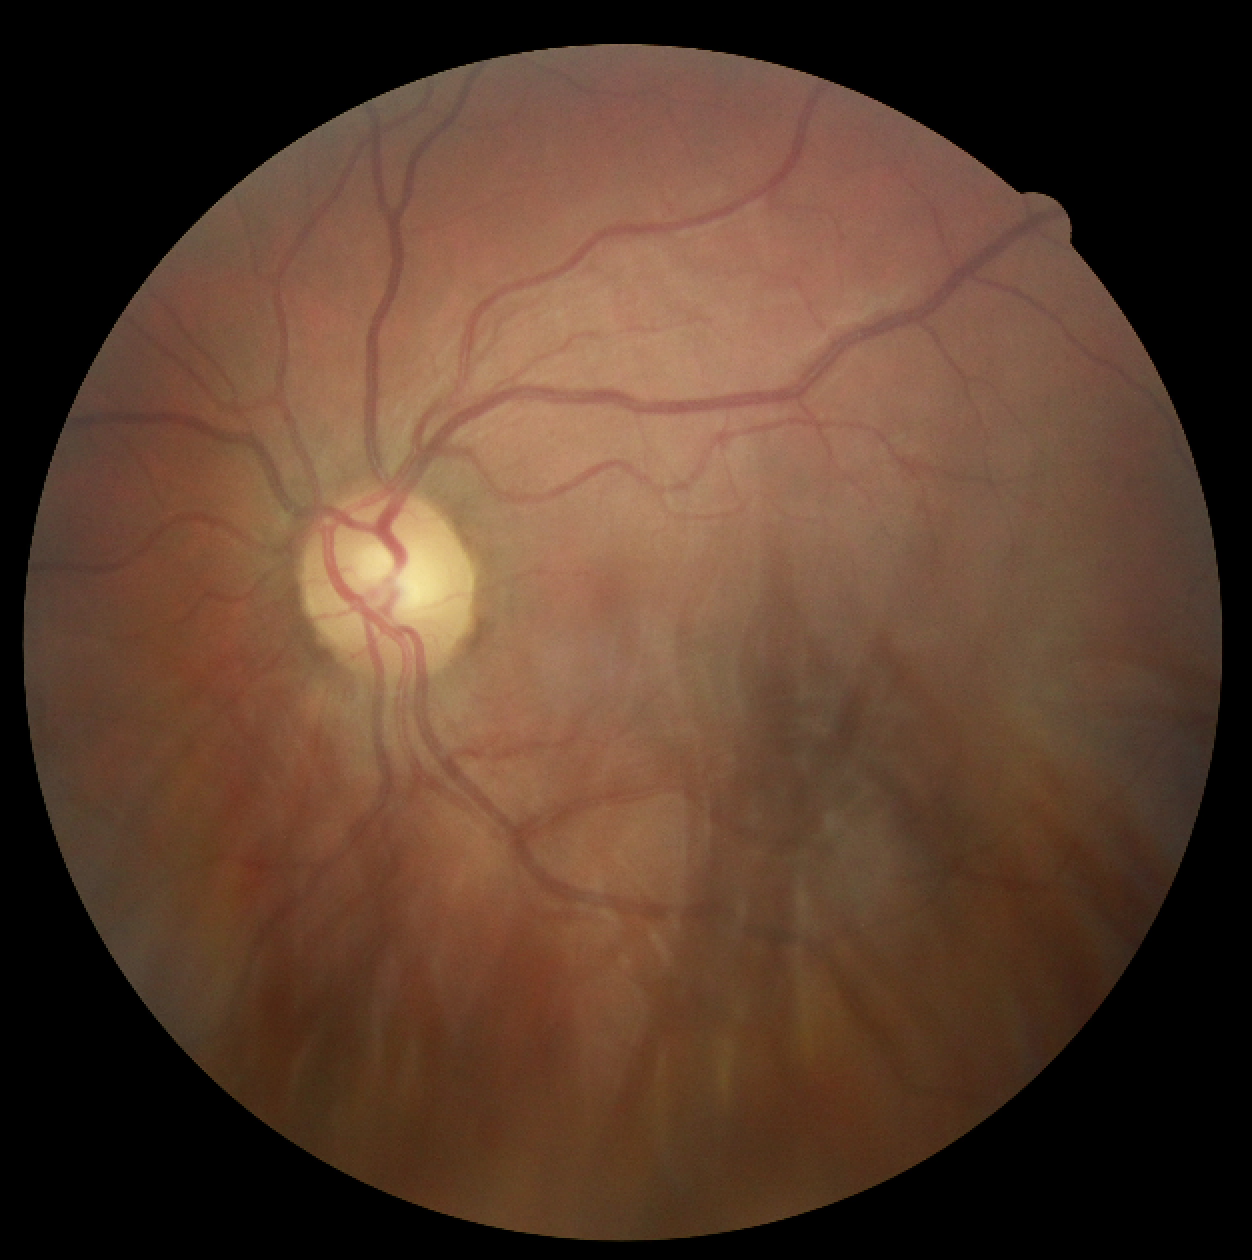

X-A Data

We chose the diabetic retinopathy dataset introduced by [32] both for its clinical impact and the privacy-sensitive nature of retinal data. The dataset consists of macula-centered retinal fundus images primarily sourced from EyePACS and was graded by 54 opthalmologists or opthalmologist trainees using the International Clinical Diabetic Retinopathy scale [7] into ‘none’, ‘mild’, ‘moderate’, ‘severe’, or ‘proliferative’ ratings for the severity of the condition.

We were able to obtain a subset of around 35,126 images of the dataset, with a label distribution of 25,810 ‘none’, 2,443 ‘mild’, 5,292 ‘moderate’, 873 ‘severe’, and 708 ‘proliferative’ diagnoses. Scans from both the left and right eye were sourced from each patient. To compare our results to the replication study performed by [66], we group the ‘none’ and ‘mild’ labels to a ‘0’ label and the ‘moderate’, ‘severe’, and ‘proliferative’ labels to a ‘1’ label to reframe our problem into a binary classification task. We randomly subsampled our dataset to get an even split between our two labels, and following the guidelines recommended by [32] we use an 80-20 split for training and test data.

Before using the retinal images with our network, we perform some preprocessing on the raw images. The scans are scaled to , the standard ImageNet input size, with cropping performed using edge detection to reframe the images. To normalize the colors and lighting, each image is subtracted by the local average color of each image, after which the local average is mapped to grayscale. Random rotation is performed on the image to make the model invariant to left/right eye positioning and for general augmentation. Samples of the data we use are provided in Figure 5.